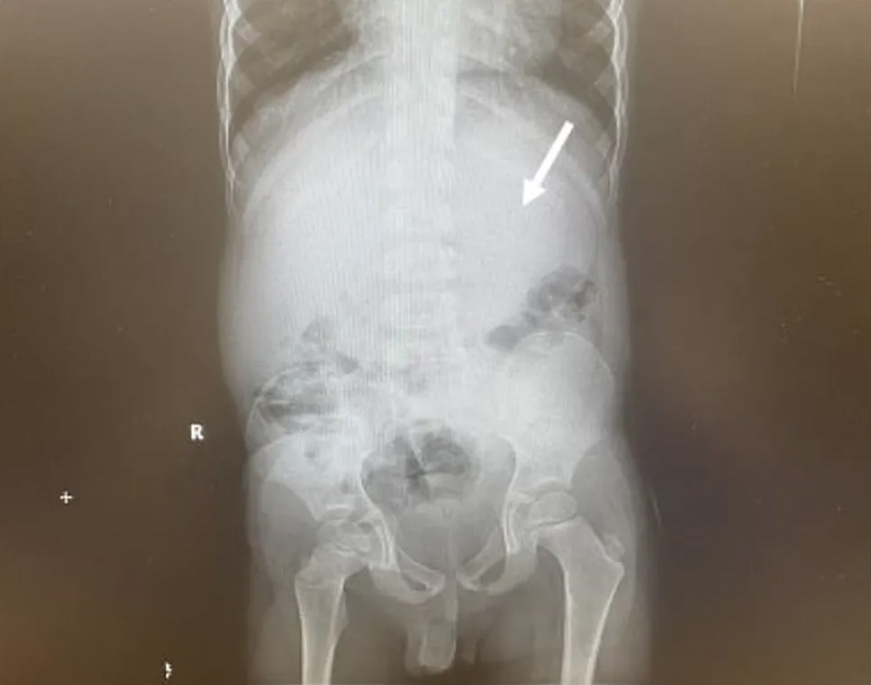

Tomografias computadorizadas mostraram que o menino tinha uma grande massa presa no estômago, também conhecida como bezoar, que ocupava quase 25% do espaço.

Segundo o jornal Mirror, a equipe médica teve que puxar o pedaço de chiclete de volta pela sua garganta depois que as tomografias mostraram que estava alojado em seu estômago.